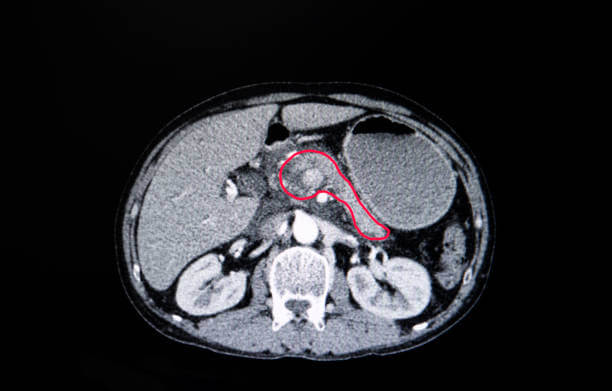

췌장암 병기와 수술 가능 여부

췌장암 병기 췌장암은 병기에 따라 수술가능 여부가 판가름 나는 질병으로 수술로 종양을 떼어 낼 수 있을 경우 생존확률이 크게 개선되는 상황이어서 암에 대해 인지를 하고 난 이후에는 췌장